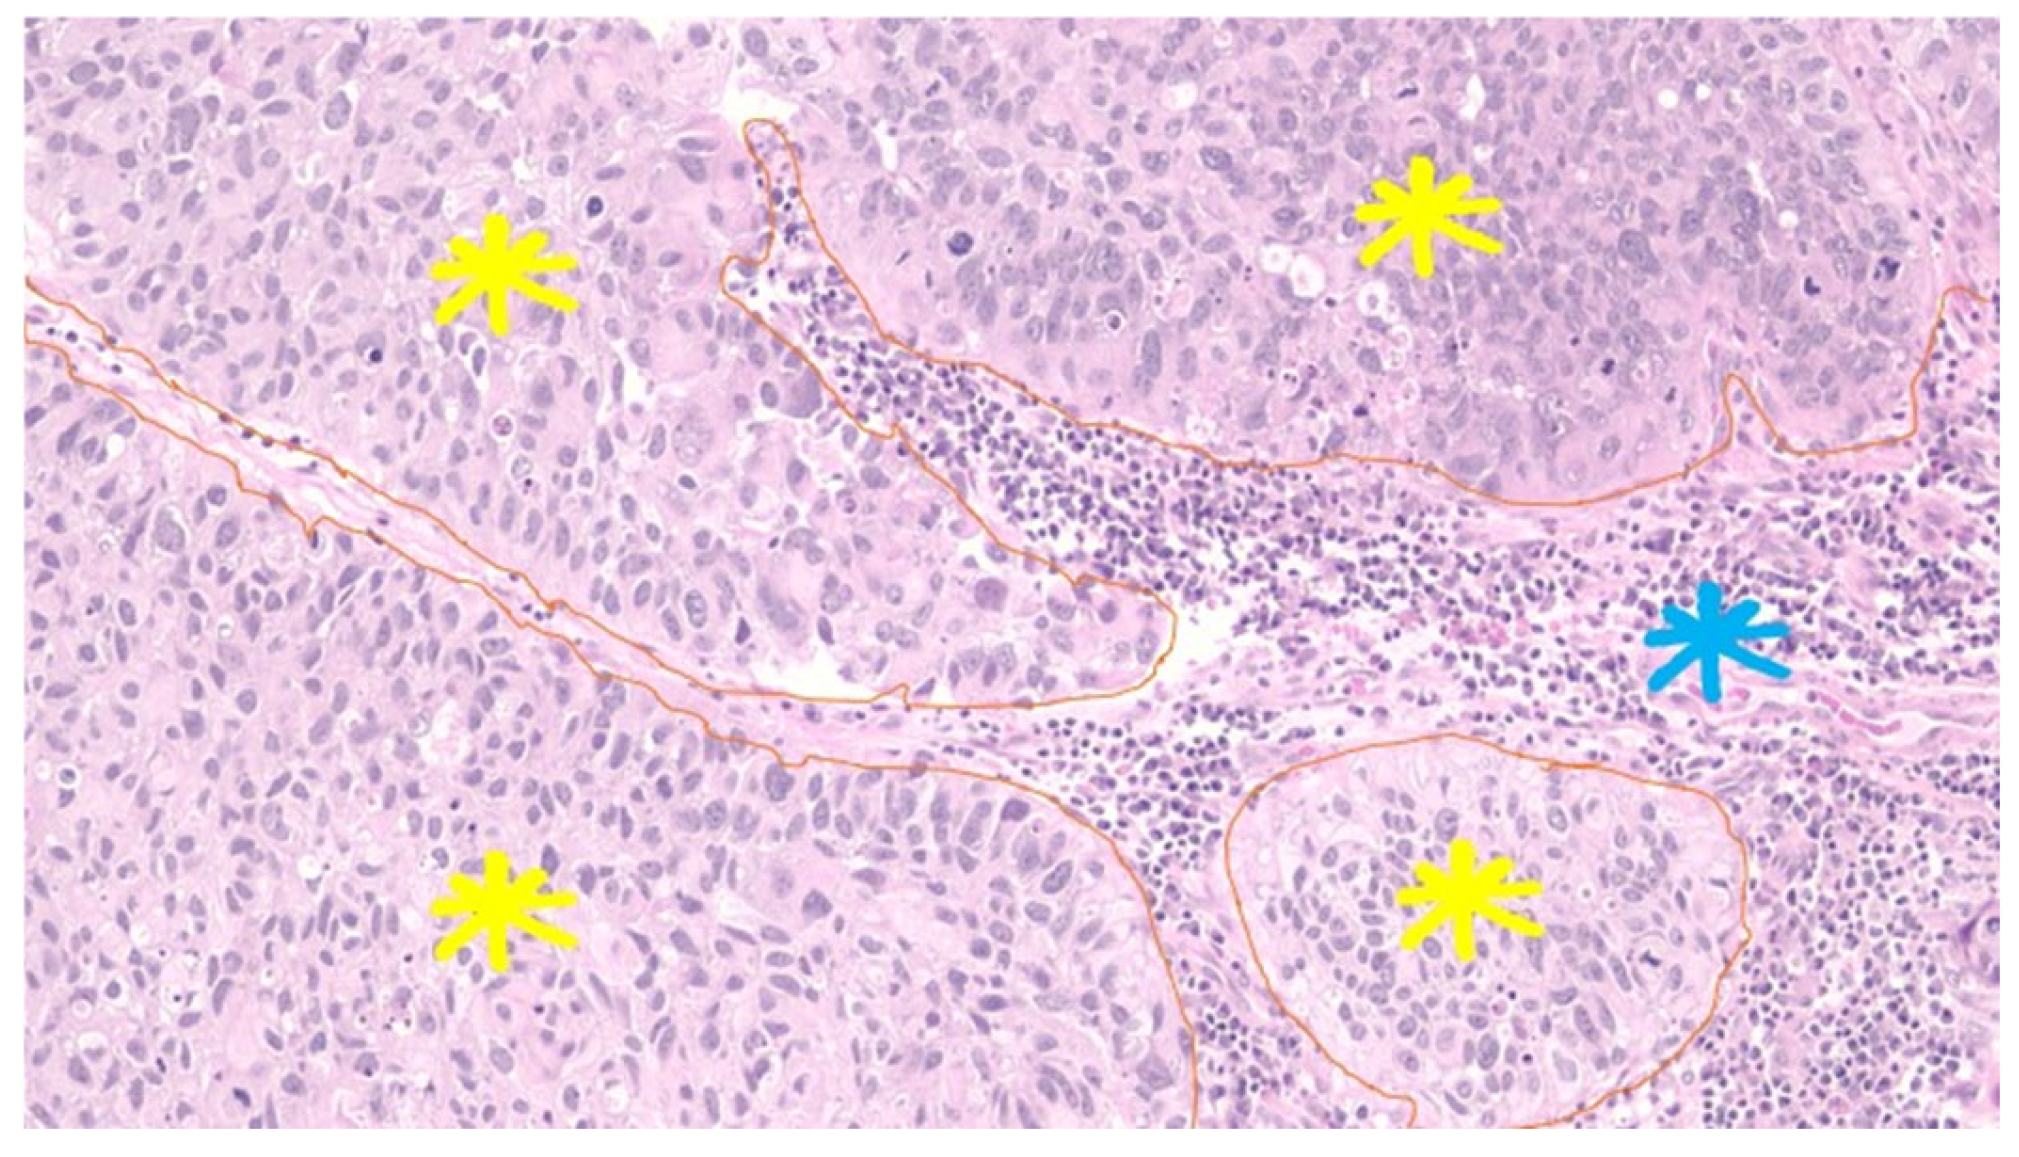

8. Tertiary Lymphoid Structures (TLS)